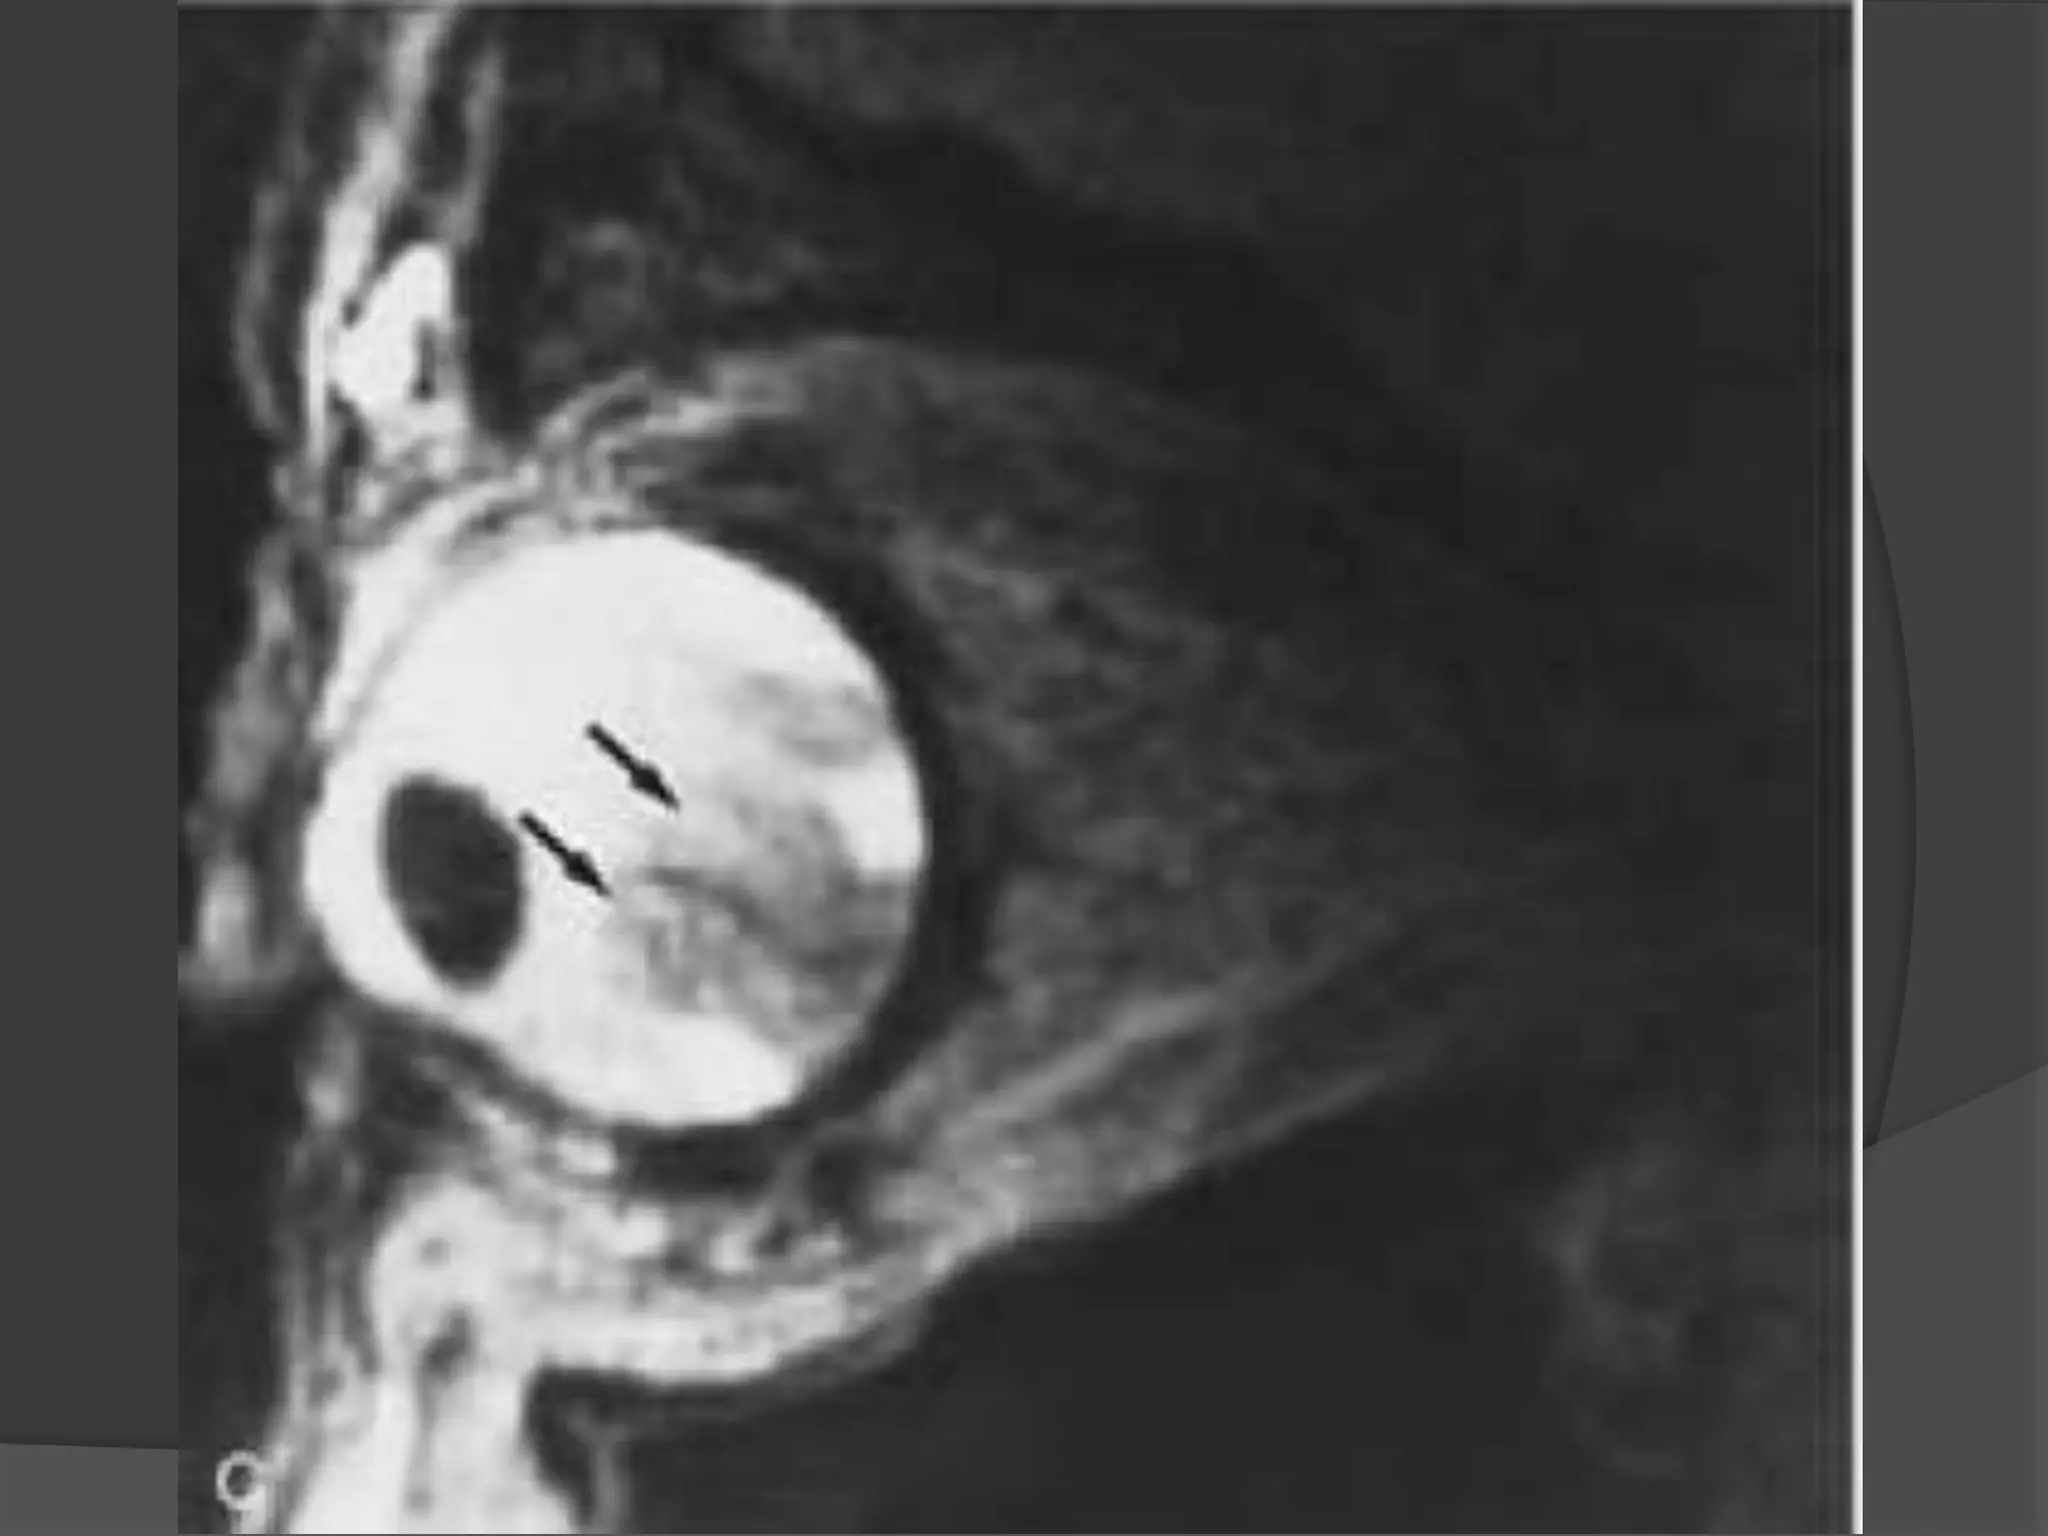

• #12 Retinal detachment. A - White arrows is retinal detachment B – Black arrows – hyperintense areas - subretinal exudate

• #13 Total retinal detachment. Axial T2-weighted MR image shows a detached retina (arrows) with the characteristic V-shaped configuration with the apex at the optic disc. Hypointensity of the left globe is caused by injection of silicone oil into the vitreous, which also has escaped into the subretinal space. The arrowhead points to residual subretinal fluid not replaced by silicone oil.

• #14 Retinal detachment. T1-weighted coronal MR image shows the characteristic appearance of retinal folds (arrows) and a hyperintense subretinal exudate (E ).

• #15 Serous choroidal detachment. Axial CT scan shows two prominent linear images (solid arrows) in the right eye. Because of the anchoring effect of posterior ciliary arteries and nerves, detached leaves of choroid usually do not appear to converge at the disc, unlike retinal leaves in retinal detachment. The suprachoroidal space (S) is isodense with vitreous, indicating serous choroidal detachment. The enlarged right globe results from known congenital glaucoma. Note the postsurgical changes in the left eye and the scleral-encircling silicone band (curved arrow).